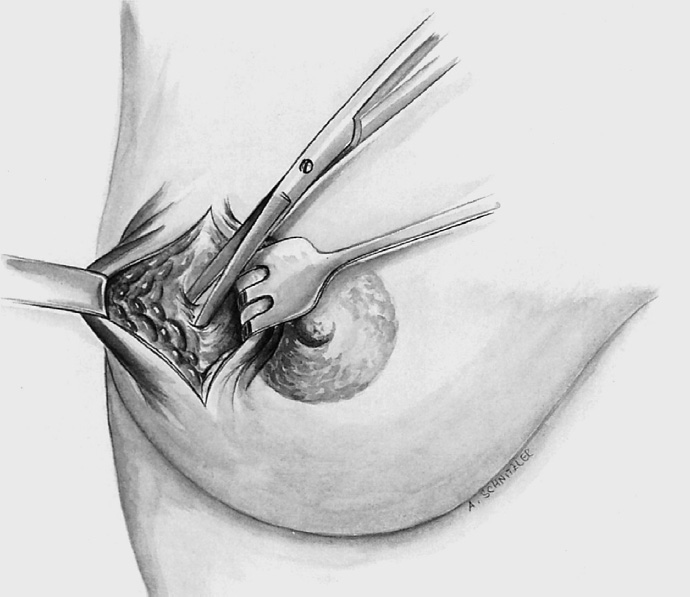

The segment containing the tumor is dissected sharply with dissecting scissors or electrocautery to obtain an initial adequate resection margin under digital control or sonographic direct visualization.

The segment containing the tumor is dissected sharply with dissecting scissors or electrocautery; an adequate initial resection margin should be obtained under digital control or sonographic direct visualization. A specimen sonogram or mammogram is performed when needed.

The adjacent parenchyma is mobilized subcutaneously so that the defect can be filled with lobes of breast tissue. Mobilization means exposing the breast relative to the skin or muscle to achieve adequate mobility of < 25% or > 25% as required.

Segmental excision of the area containing the tumor with resection margins as wide as possible to meet oncological criteria. Oncoplastic techniques should be used to achieve maximal oncological safety and avoid subsequent further resection.

To cover the defect, the glandular lobes are mobilized from the adjacent parenchyma after subcutaneous dissection. The principle of intramammary lobe creation is to mobilize large parts of the breast (> 25%) either relative to the skin or relative to the pectoralis muscle. This “liberation” of the breast from one of its two planes of fixation allows adequate dissection and rotation of sufficient breast tissue. The Y-flap and rotation flap shown in Chapter 3.2.1 are examples of intramammary dissection.

Following the skin incision, the superior skin envelope is dissected off the breast, that is, in a superior, medial, and lateral direction. This step is crucial as it provides maximum access to the breast, enabling reduction to be “tailored” exactly to the tumor.

The breast containing the tumor is resected in classic segmental fashion along the tumor axis. In purely cosmetic reduction, tissue is removed mainly in the upper outer part and somewhat less in the superior and medial part. It is important to leave sufficient breast tissue behind the areola and in the cranial part as otherwise the projection of the areolar region will be poor after it is sutured. Additional tissue can be resected lateral to the inferior pedicle on right and left.